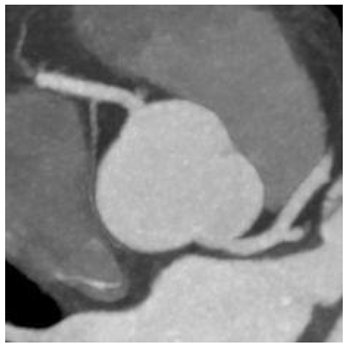

3.2. Radiologic

| Type | Diagram | CT Image |

|---|---|---|

| Normal | ![]() | ![]() |

| I | ![]() | ![]() |

| II | ![]() | ![]() |

| III | ![]() | ![]() |

| Radiologic Feature | Types | Number of Patients | % |

|---|---|---|---|

| Origin | I | 27 | 48 |

| II | 14 | 25 | |

| III | 15 | 27 | |

| Course | Between aorta and pulmonary trunk “malignant” | 0 | 0 |

| Between aorta and left atrium “benign” | 56 | 100 | |

| Ostia | Round (normal) | 42 | 75 |

| Oval | 14 | 25 | |

| Slit | 0 | 0 | |

| Angle | ≤45 | 39 | 70 |

| >45 | 17 | 30 | |

| Intramural course | 29 | 52 |